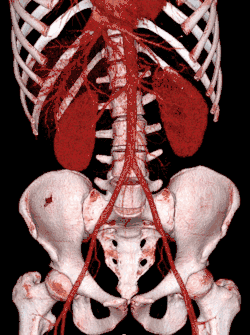

Vascular Imaging

Computed tomography angiography (CTA) is a type of contrast CT to visualize the arteries and veins throughout the body.[111] This ranges from arteries serving the brain to those bringing blood to the lungs, kidneys, arms and legs. An example of this type of exam is CT pulmonary angiogram (CTPA) used to diagnose pulmonary embolism (PE). It employs computed tomography and an iodine-based contrast agent to obtain an image of the pulmonary arteries.[112][113]